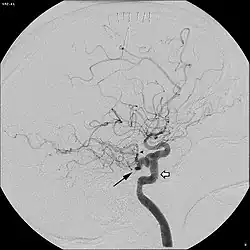

In around 0.1 to 0.6% of individuals, as sampled by magnetic resonance angiography, the trigeminal artery fails to involute and remains in the adult brain, in a condition called persistent trigeminal artery.[3] This condition is more common in women than in men, with approximately 1.8 times as many women having the condition.[6] Knowledge of a persistent trigeminal artery may be important in certain brain surgeries, as the condition is rare and an accidental cut to the artery could lead to hemorrhage.[1] Although the discovery of a persistent trigeminal artery is sometimes an incidental finding, its presence is also associated with various pathological conditions, and must therefore be considered carefully when diagnosing these conditions.[7]

A persistent trigeminal artery is associated with an increased risk of aneurysm, though some studies have suggested that this finding may be an effect of selection bias, as most individuals do not undergo the tests necessary to identify the condition.[3] Persistent trigeminal artery has been identified as a rare cause of trigeminal neuralgia, with 2.2% prevalence of persistent trigeminal artery among trigeminal neuralgia patients.[9] Surgery to move the persistent trigeminal artery away from the trigeminal nerve has been successful in treating the trigeminal neuralgia in some cases.[10] In some cases, presence of a persistent trigeminal artery concurs with hypoplasia of the basilar artery, in which case the internal carotid artery is responsible for most blood flow to the upper pons, cerebellum, midbrain, and parts of the temporal and occipital lobes, meaning that anything disrupting blood flow in the internal carotid artery could lead to ischemia in these regions.[11] In addition, persistent trigeminal artery has been associated with vertebrobasilar insufficiency, brainstem ischemia, and carotid cavernous fistulae.[2]